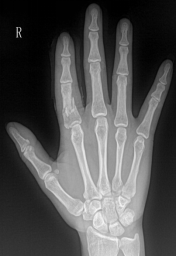

类风湿性关节炎

多发性、非特异性慢性滑膜炎症为主要表现的全身性疾病

多见于20-40女性

受累关节多呈对称性,以手足小关节为主

影像表现:①关节软组织肿胀;②关节间隙变窄、关节面边缘骨侵蚀;③软骨下多发囊样透亮区;④骨质疏松;⑤ 关节畸形和关节强直

F,55Y